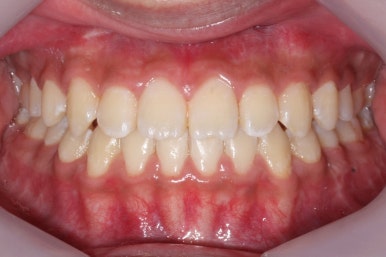

치료 종료 후의 모습입니다.

부산주걱턱교정 키다리아저씨치과에서 이번 환자분 치료에 걸린 총 기간은 1년 4개월이였고, 수술 전 교정 10개월과 수술, 수술 후 교정은 4개월 가량이 걸렸습니다.

주걱턱 경향이 사라졌고, 그에 따라 입술 형태나 웃는 모습, 교합 등등 모든 면에서 개선되었습니다.

전후사진을 비교해 보겠습니다.

양악수술을 통해서 얼굴 모습이 미적으로 많이 개선되었습니다.

뒤집어진 U자형의 입술도 개선되었고, 웃을 때 어금니가 내려와 있던 모습도 많이 개선되었습니다.